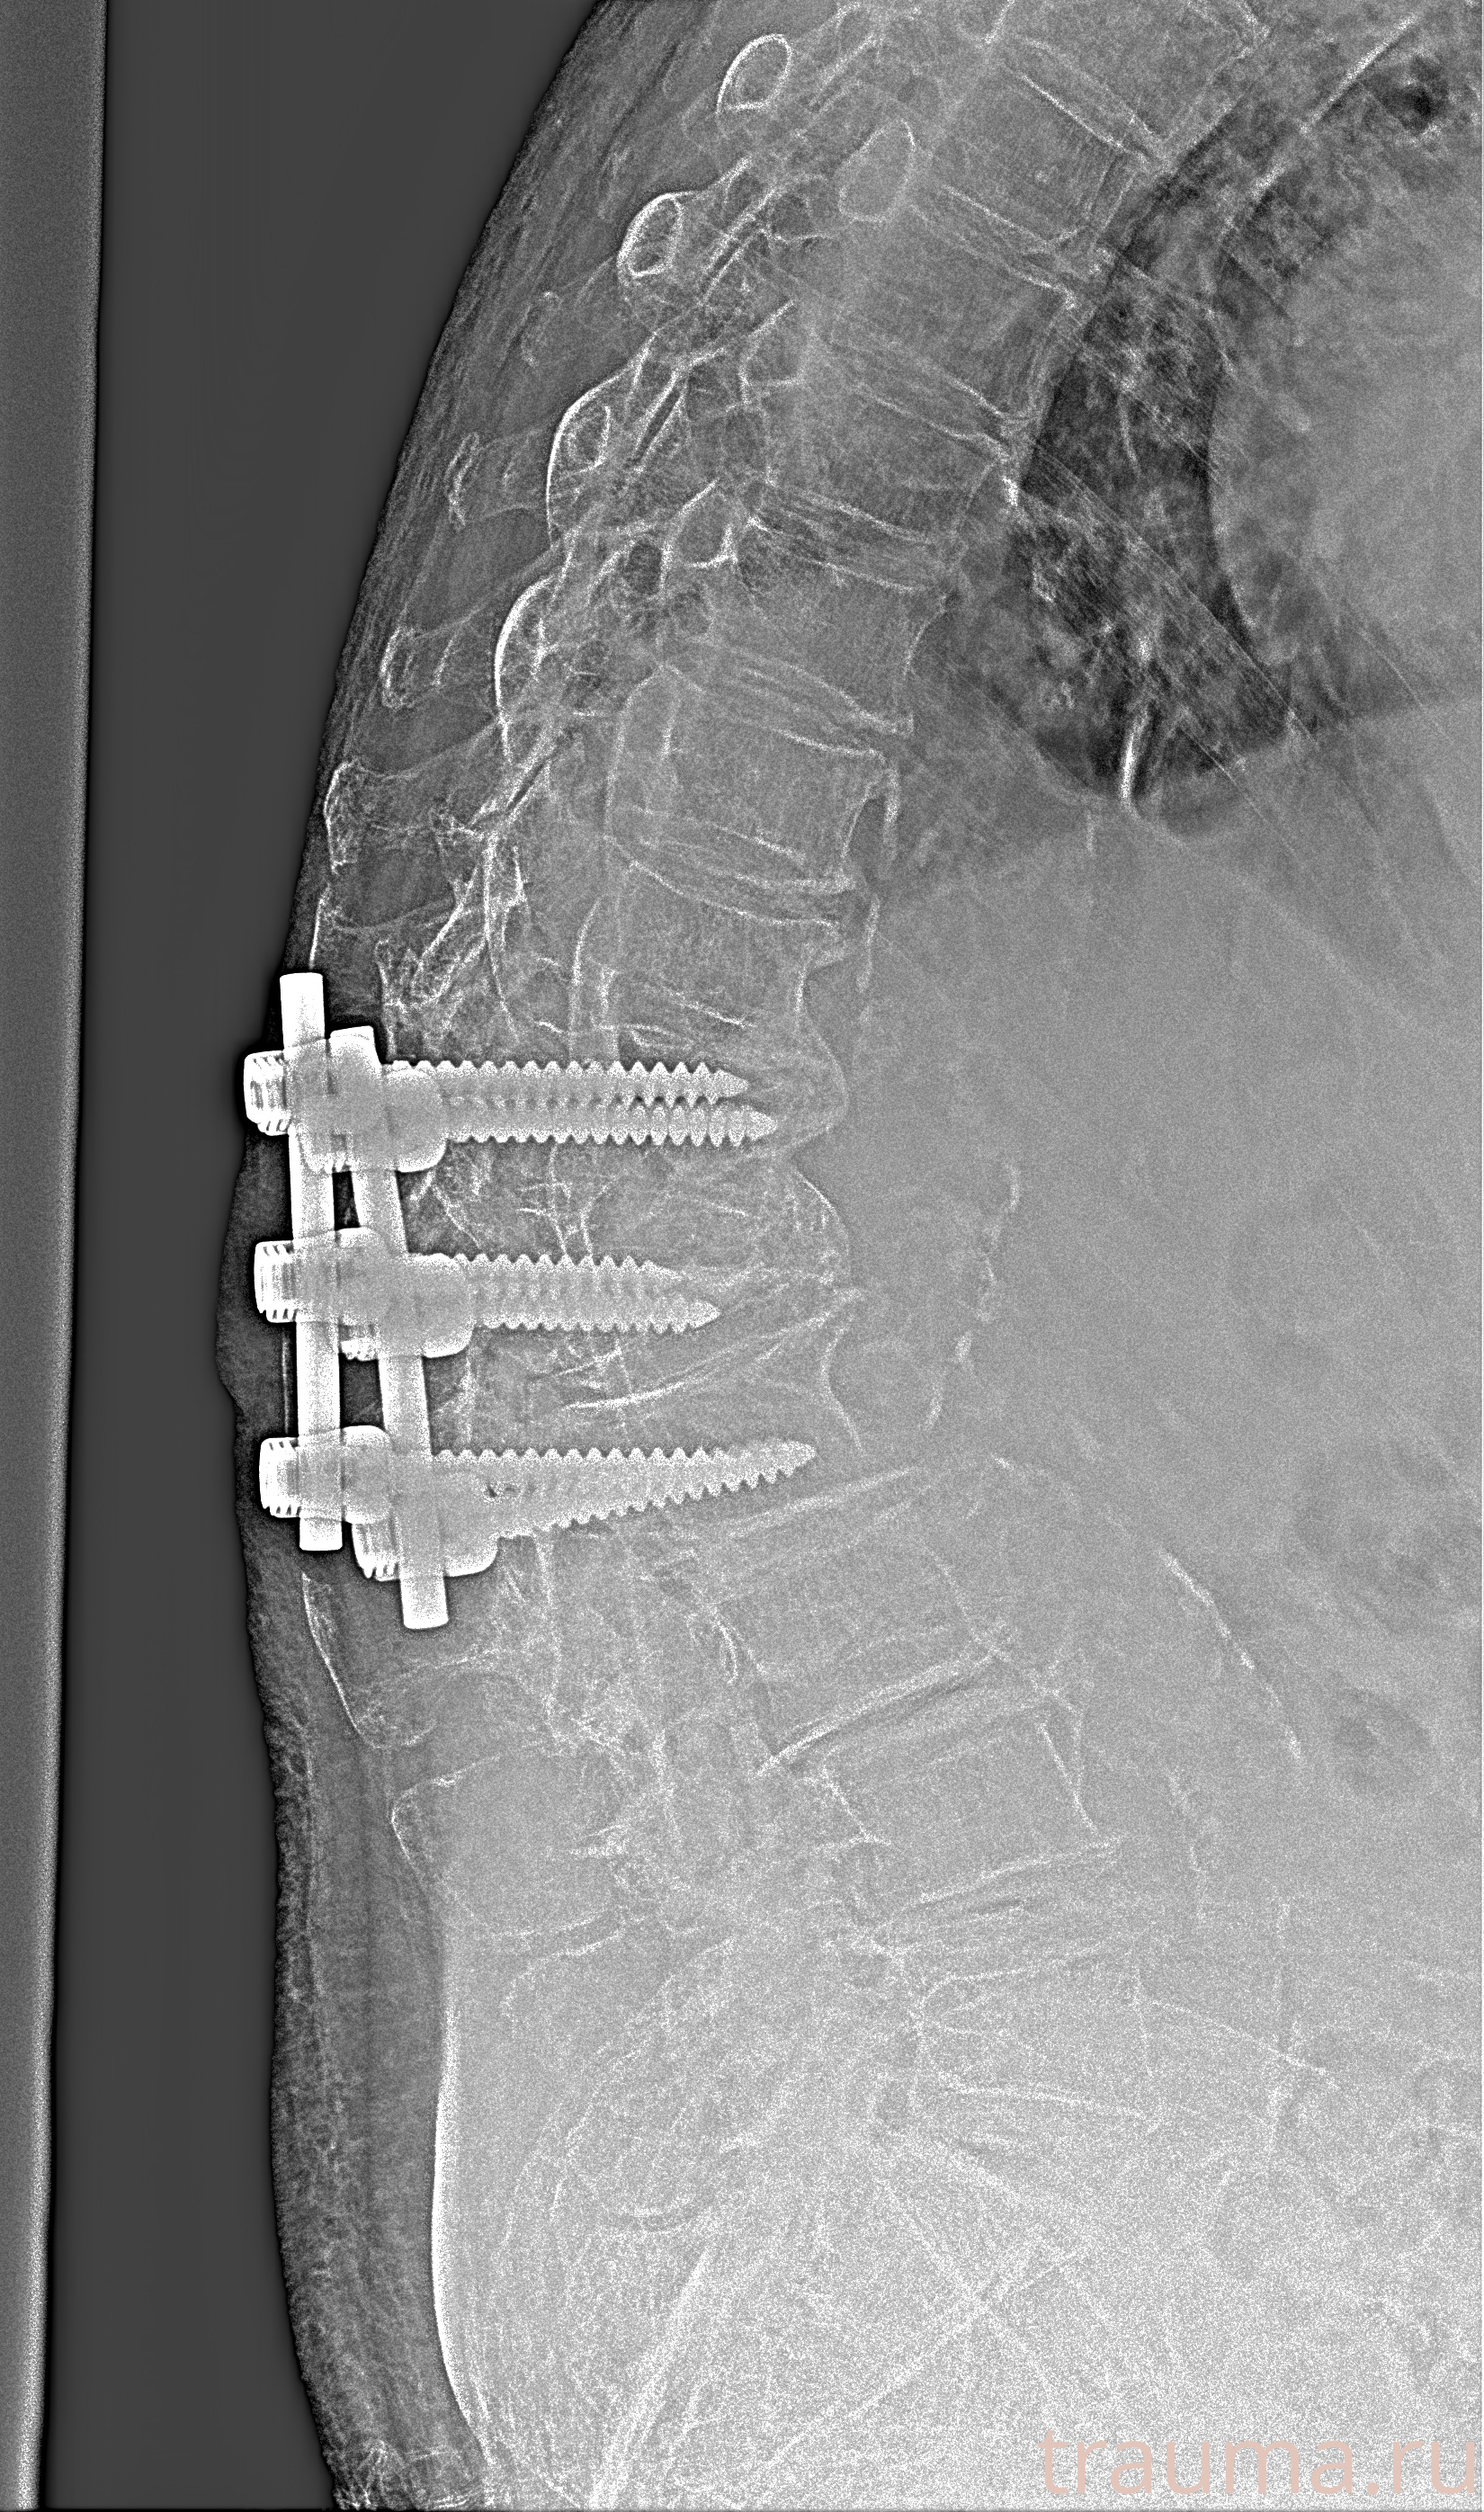

Рентгенограммы